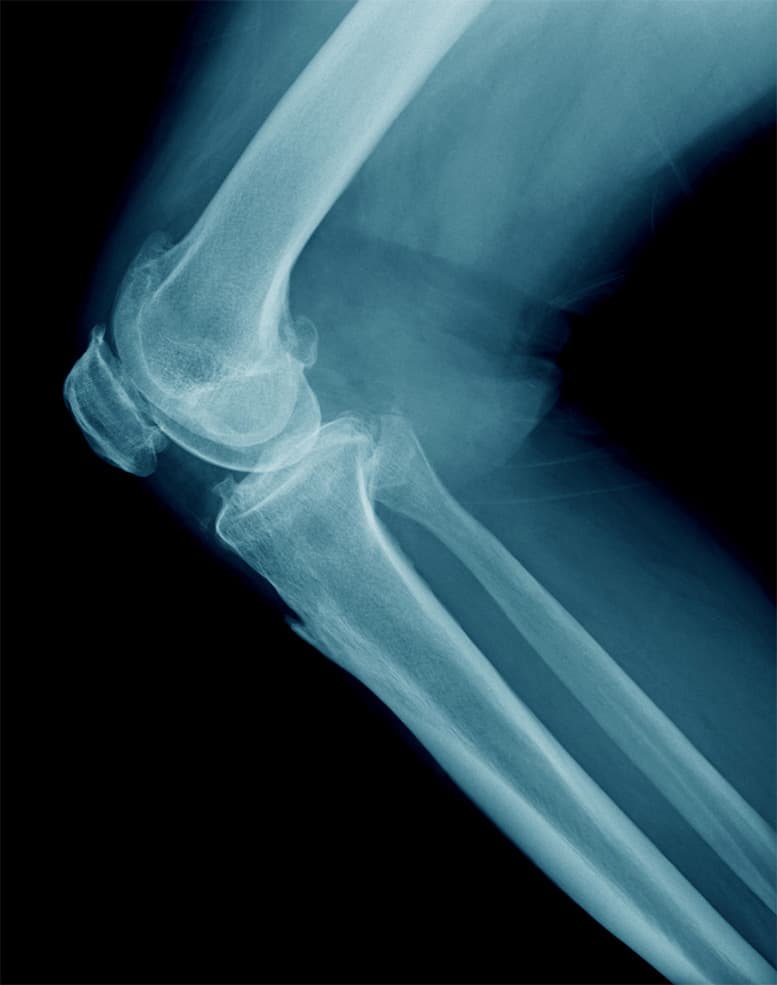

La gonartrosi, o artrosi del ginocchio, è una patologia degenerativa e progressiva, molto frequente con l'avanzamento dell'età con prevalenza maggiore nel sesso femminile, che provoca dolore e rigidità articolare, specialmente al mattino.

Una lesione meniscale si verifica durante movimenti di iperflessione, in cui il menisco viene compresso dal condilo femorale, oppure, nella maggior parte dei casi, durante eventi traumatici derivanti da movimenti combinati di flessione e rotazione.